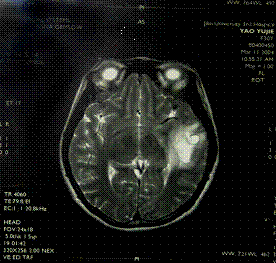

(二)磁共振(MRI)高磁場(1.5Tesla)的MRI在起病1小時內就可能顯示皮質表面和後顱凹的梗塞。起病6小時後的梗塞幾乎都能被MRI顯示,表現為T1加權低信號和T2加權高信號。MRI的缺點為價格高,成像時間長,不適用於重危病人、不合作者和裝有金屬假牙和心電起搏器的病人。